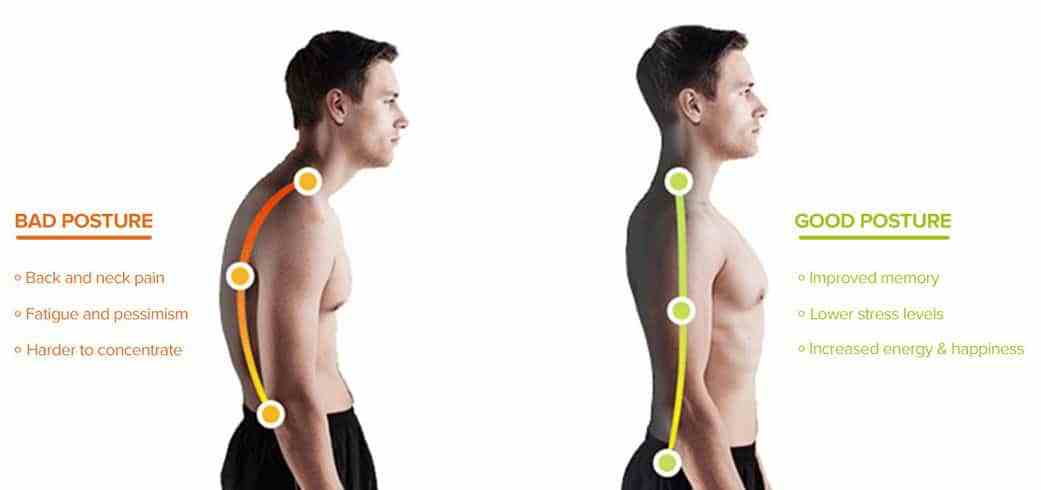

وضعیت نامناسب بدن

وضعیت نامناسب بدن هنگام نشستن، ایستادن یا خوابیدن یکی از دلایل رایج بروز انواع کمردرد است. وقتی ستون فقرات در حالت غیرطبیعی قرار میگیرد، فشار زیادی به مهرهها و عضلات اطراف آن وارد میشود. استفاده طولانیمدت از صندلی غیراستاندارد یا خم شدن بیش از حد هنگام کار با لپتاپ میتواند زمینهساز درد مزمن کمر باشد.

با اصلاح وضعیت بدن و رعایت اصول ارگونومی میتوان از بروز بسیاری از مشکلات جلوگیری کرد. فیزیوتراپیستها معمولاً آموزشهای اصلاحی در این زمینه ارائه میدهند تا فرد بتواند با تغییر عادات روزمره، سلامت ستون فقرات خود را حفظ کند. استفاده از صندلی و میز استاندارد، قرارگیری صحیح گردن و شانهها و پرهیز از خمیدگی مداوم، از مهمترین توصیهها هستند.